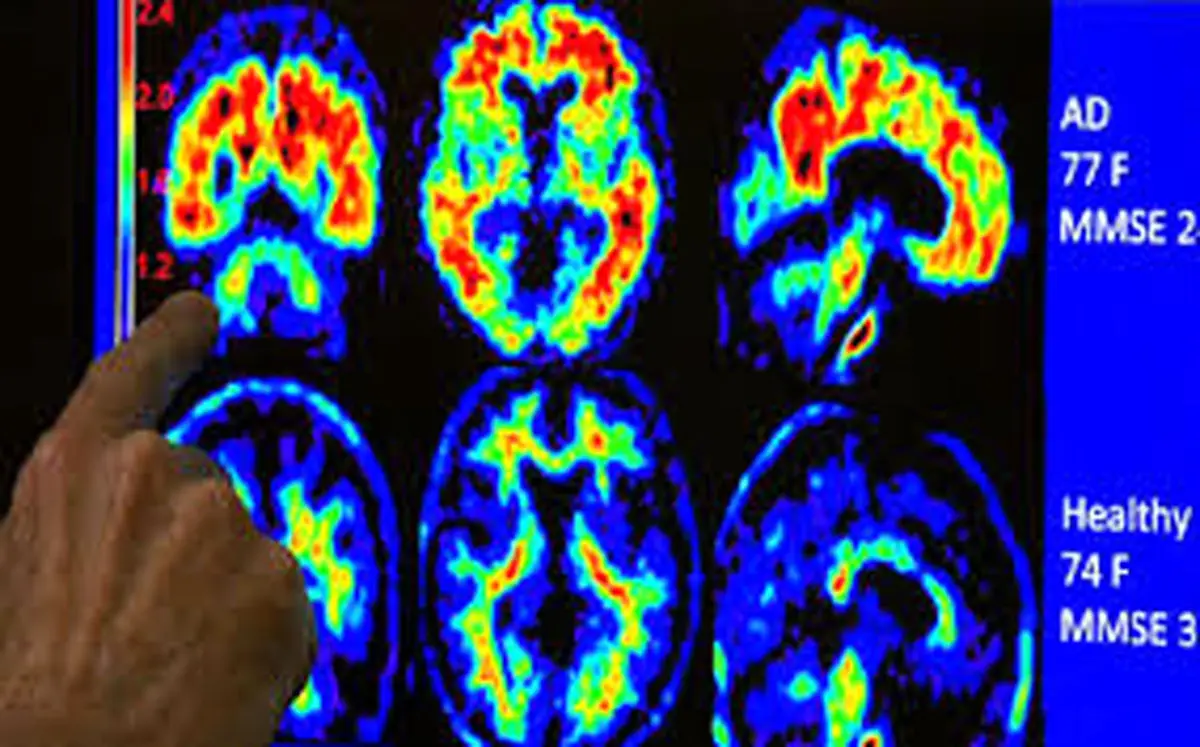

درمان آلزایمر با امواج مافوق صوت

محققان دانشگاه توهوکوی ژاپن «Tohoku» با استفاده از امواج مافوق صوتی موفق به درمان اختلال شناختی در موش های مبتلا به دمانس شدند.